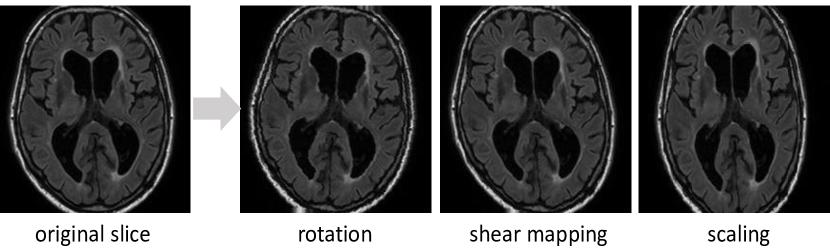

3.1.1 Data augmentation

Data augmentation is an effective way to equip the deep networks with desired invariance and robustness properties when training data are limited. In case of MR images among different subjects and scanners, due to variations of head orientations, voxel sizes and WMH distribution, we primarily need rotation and scale invariance as well as robustness to shear transformation. For each axial slice, three transformations including rotation, shear mapping and scaling were applied, each within a parameter range. The parameter range represents the variation in different aspects between subjects in clinical practice; for example, rotation of brain is in the range of [-15°, 15°]. Table 2 lists the parameter range for each of the three transformations. It should be noted that the scaling used in the training of the algorithm was in the range of (0.9, 1.1), representing the range of voxel size ratios in the training data sets (Table 1), while some test sets had noticeable larger ratios (a factor of 1.21 between the PETMR and the Singapore data set). This indicates the robustness of our approach, but also leaves potential room for improvement in future studies exploring the optimal scaling of the data during training.

Figure 3 shows an example of the resulting slices after applying the transformations. After data augmentation, we obtain a dataset ten times larger than the original one.

Refer to caption

Figure 3: An example of data augmentation result. From left to right: the original axial slice, slice after rotation, slice after shear mapping and slice after scaling.